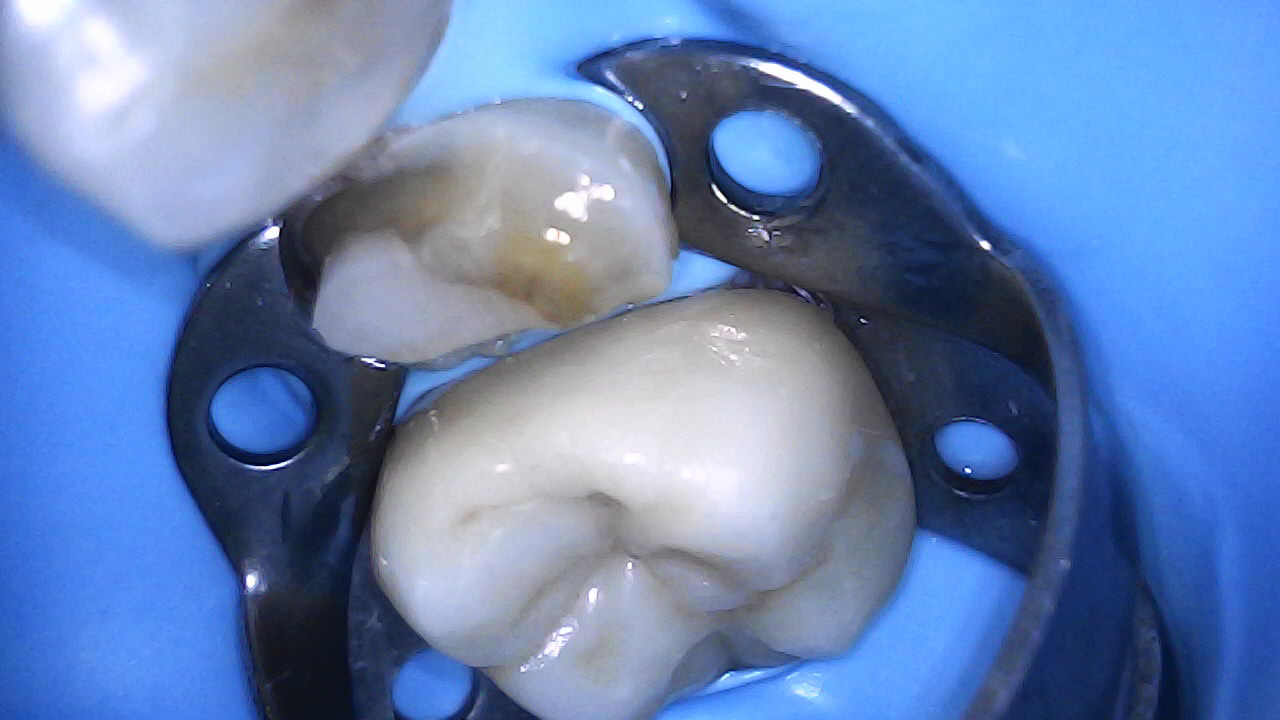

15 buccal fracture

15 Fractured Buccal cusp

Tooth prep and IDS